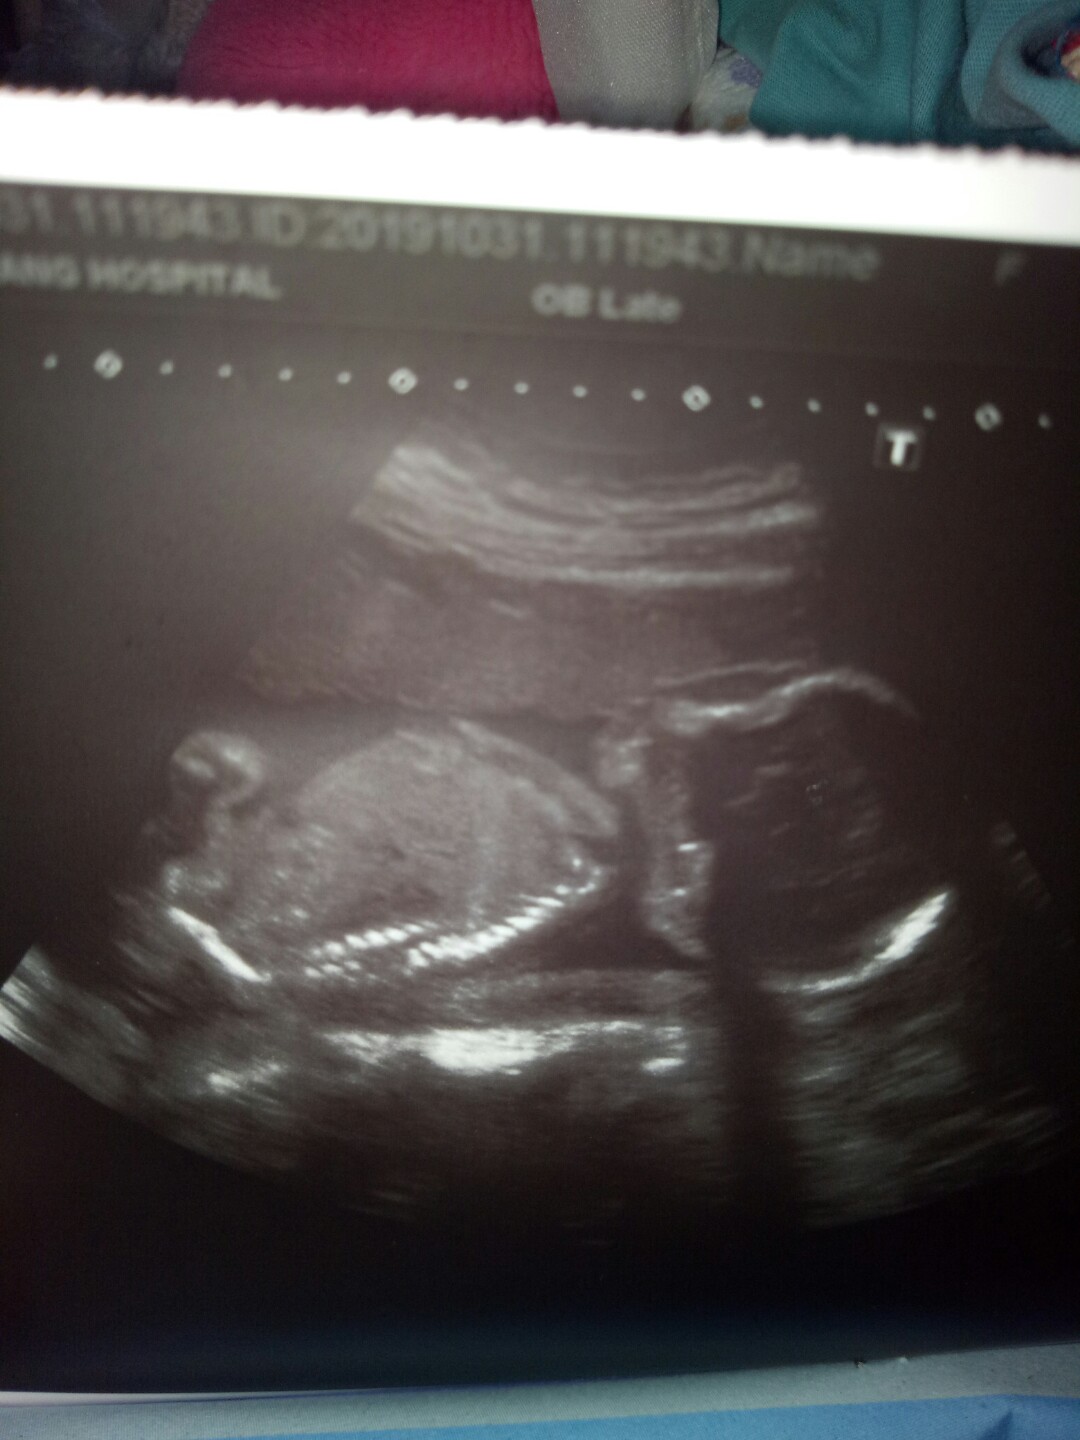

บ้านนี้ตอนห้าเดือนค่ะ